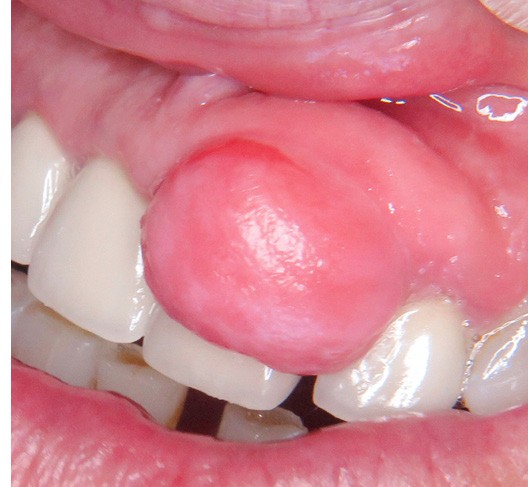

2. Épulis fibreux

- Nodule ferme, muqueuse de couleur normale (fig. 2a et b).

- Stade évolutif tardif de la forme inflammatoire.

- Histologie : collagène abondant, vascularisation réduite, infiltrat discret. Il peut s’agir d’une forme transitionnelle avec épulis fibroblastique ulcéré calcifiant. On observe alors des fibroblastes nombreux, moins de collagène, possible métaplasie osseuse (fig. 2c).